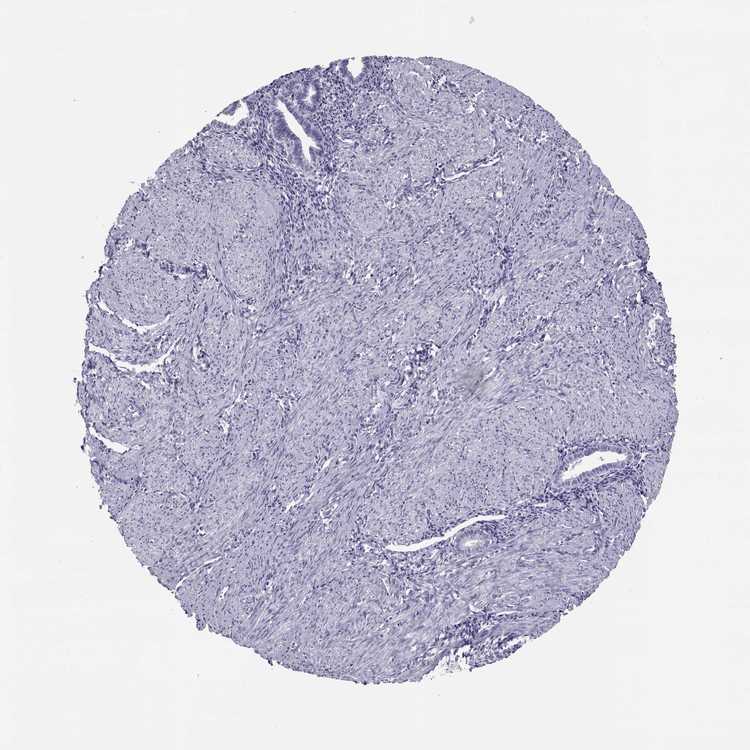

ENDOMETRIUM 1 - Antibody stainingi

Antibody staining in the annotated cell types in the current human tissue is reported as not detected, low, medium, or high, based on conventional immunohistochemistry profiling in selected tissues. This score is based on the combination of the staining intensity and fraction of stained cells.

Each image is clickable and will lead to virtual microscopy that enables deeper exploration of all samples and also displays staining intensity scores, fraction scores and subcellular localization as well as patient and tissue information for each sample.

Antibody HPA057790

Cells in endometrial stroma Not detected

Glandular cells Not detected